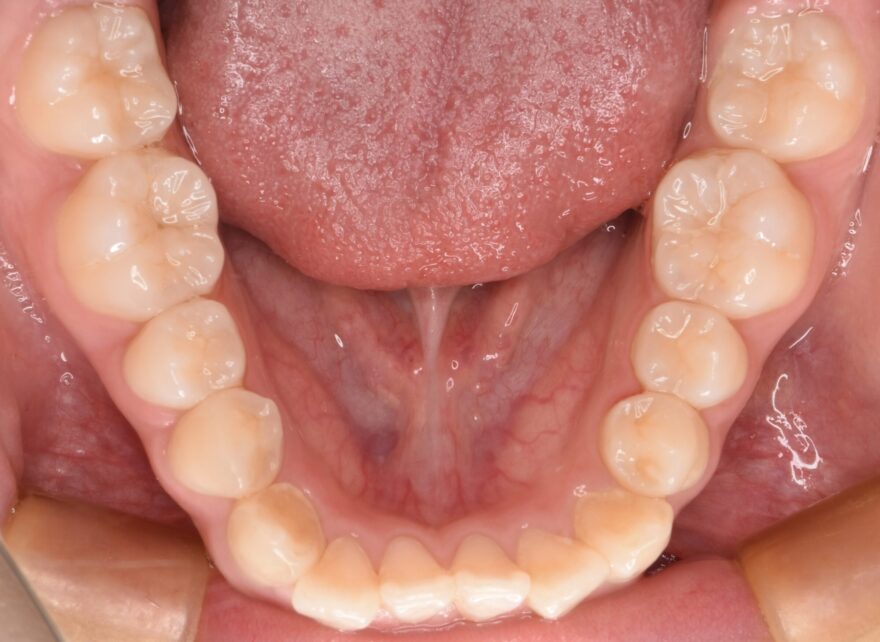

治療後の口腔内写真

約2年の動的期間(歯を動かす時期)で、ここまで整った歯並びになりました。

インビザラインでもワイヤー矯正でも、最終的な仕上がりに差はありません。

八重歯が完全に治りました。

下顎の前歯にもワイヤーによる保定装置を装着しています。